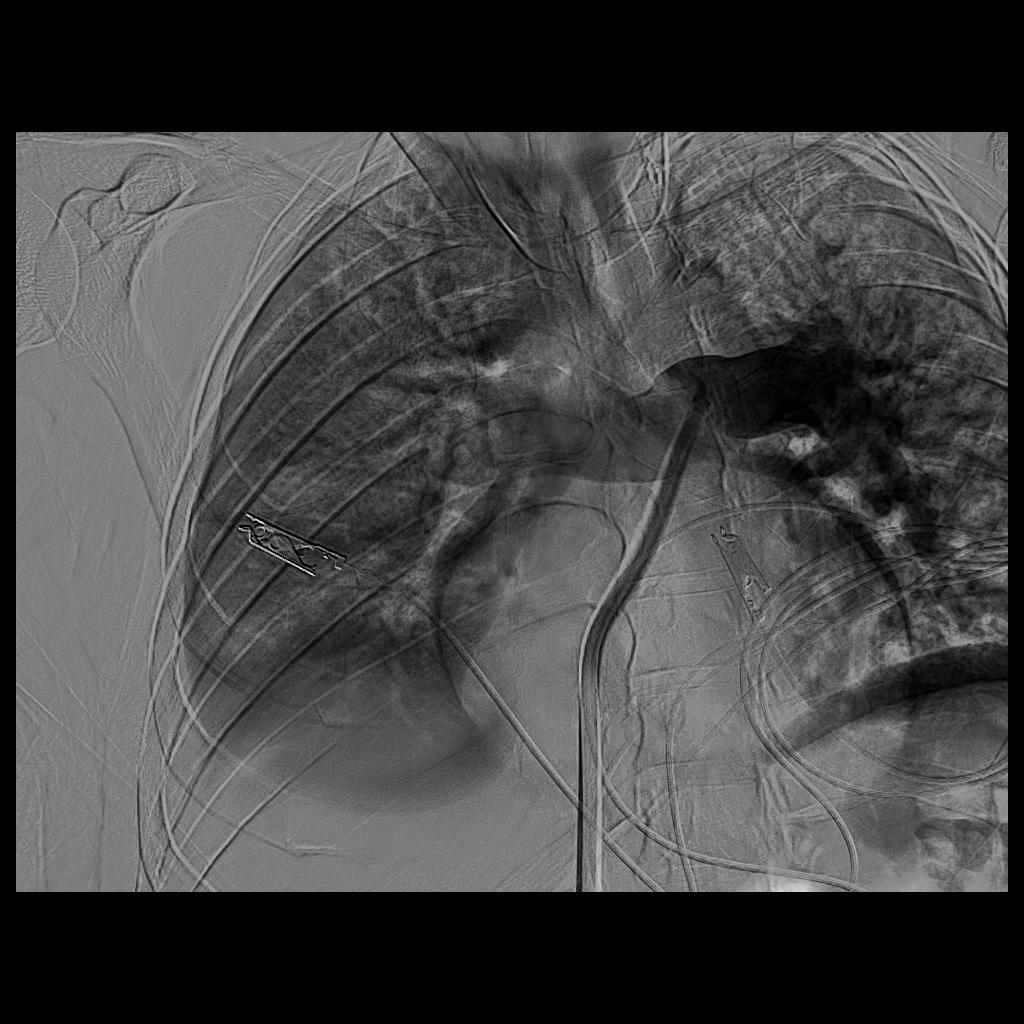

وكان المريض قد نُقل بشكل إسعافي من أحد المستشفيات وهو في حالة حرجة ، نتيجة معاناته من ضيق شديد في التنفس وانخفاض حاد في مستوى الأكسجين ، إثر انسداد كامل في الشريان الرئوي الرئيسي بسبب خثرات وريدية عميقة ظهرت بعد خضوعه لعملية منظار لمفصل الركبة.

وبفضل سرعة الاستجابة وجاهزية فريق الأشعة التداخلية جرى التدخل العلاجي العاجل وفتح الشريان الرئوي وسحب الجلطة بالكامل بدقة عالية ، ما أدى إلى تحسّن فوري في العلامات الحيوية واستقرار الحالة دون تسجيل أي مضاعفات.